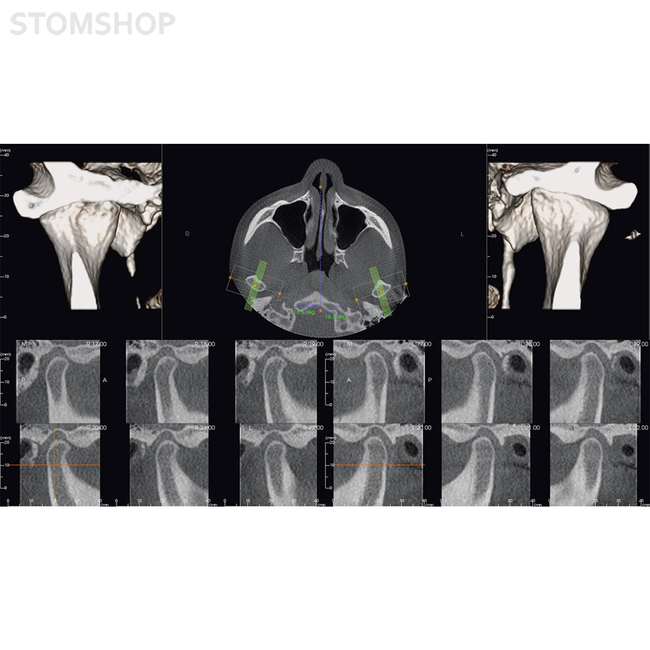

Гнатология: индивидуальная диагностика нижней челюсти

Необходимое вам программное обеспечение будет установлено в OP 3-D Vision во время эксплуатационного запуска. В перечне предустановленного ПО есть поддержка трехмерной рентгенографии, хирургические шаблоны для планирования имплантатов и имплантационной хирургии, другие варианты применения по выбору.

Ваша рентгенографическая система KaVo OP 3-D Vision готова для будущей эксплуатации: вы можете заказать DTX Studio, новую программную платформу, разработанную в виде целостной системы организации технологических процессов. DTX Studio постоянно оптимизируется и охватывает все области современной стоматологии и дентальной технологии в будущем. DTX Studio совместимо с операционными системами Mac и Windows. Оно будет объединять как уже существующие, так и проектируемые устройства многочисленных брендов, а также современные возможности программного обеспечения в объединенный рабочий процесс.